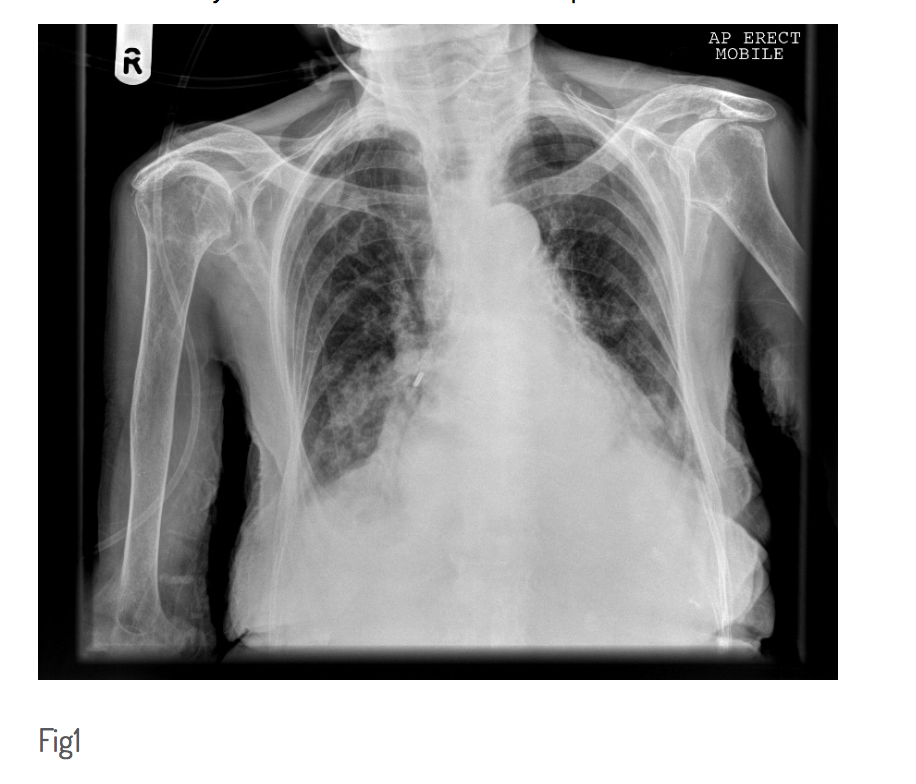

CXR

must be confirmed in right position before being flushed or used

CXR shown below

what position is the NG tube

down the right main bronchus